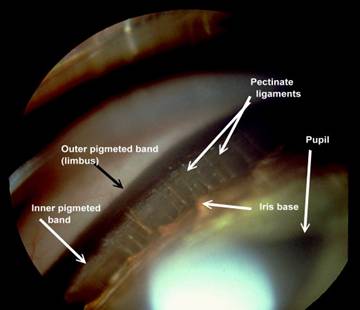

Iridocorneal angle

Figure 1: Normal canine iridocorneal angle with well-differentiated pectinate ligament.

Figure 2: Normal feline iridocorneal angle. Note the very wide space between the iris base and where the pectinate ligament attaches to the cornea.

Figure 3: A very narrow angle in cocker spaniel. The intraocular pressure in this eye was normal, but the fellow eye had markedly elevated intraocular pressure.

Figure 4: This is the iridocorneal angle of an Australian shepherd with mesodermal goniodysgenesis in which the pectinate ligament did not differentiate completely resulting in areas where a broad membrane bridges the iridocorneal angle. While the IOP was normal in this eye, it was elevated in the fellow eye where hyphema was present after the dog was kicked in the head by a horse.